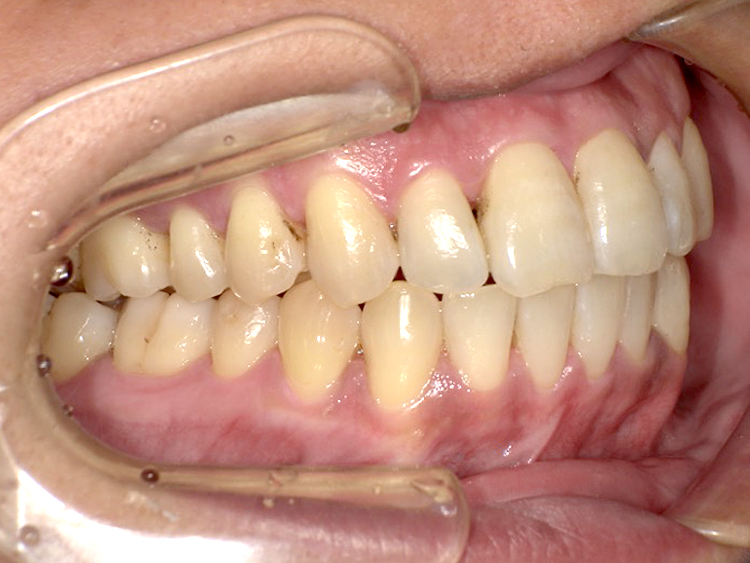

症例6

Before

After

| 主訴 | 噛み合わせが気になる |

|---|---|

| 年齢 | --- |

| 治療 期間 |

約2年11ヶ月 |

| 治療 内容 |

インビザラインコンプリヘンシブ 右上6番・左上6番ALLセラミッククラウン |

| 治療費 | ¥1,116,000(税込)/調整料含む |

| 治療のリスク | 歯を動かすことで、歯茎が下がるリスクある。 矯正終了後は、リテーナーを使用し、後戻りを防ぐ必要がある。 |